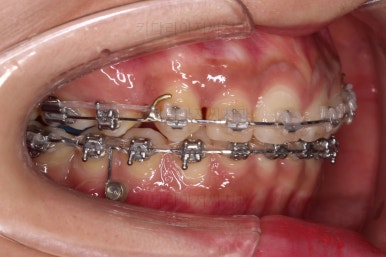

적절한 시점에 발치를 합니다.

발치는 가장 약한 치아 위주로 하게 되고요.

윗니는 이 뽑은 자리를 줄여나가고요.

아랫니는 어금니와 사랑니를 앞으로 당겨옵니다.

물론 다른 치아에 변화를 주지 않기 위해서 미니스크류를 이용합니다.

큰 틀에서는 잘 진행 중인 것 같지만 이번 경우처럼 윗니만 발치, 그리고 발치 위치가 다른 경우, 더군다나 아랫니도 어금니가 없고 사랑니를 당겨오는 경우.

미세한 치아 크기 차이로 마지막 마무리가 오래 걸리는 경우가 많습니다.

100% 중앙선이 잘 안맞는 경우가 많고 미세한 틈새가 오랫동안 잘 안닫히기도 합니다.

이번 환자분도 마찬가지로 중앙선이 100% 안맞았고, 틈새를 타이트하게 닫기 위해 시간이 좀 소요되었습니다.